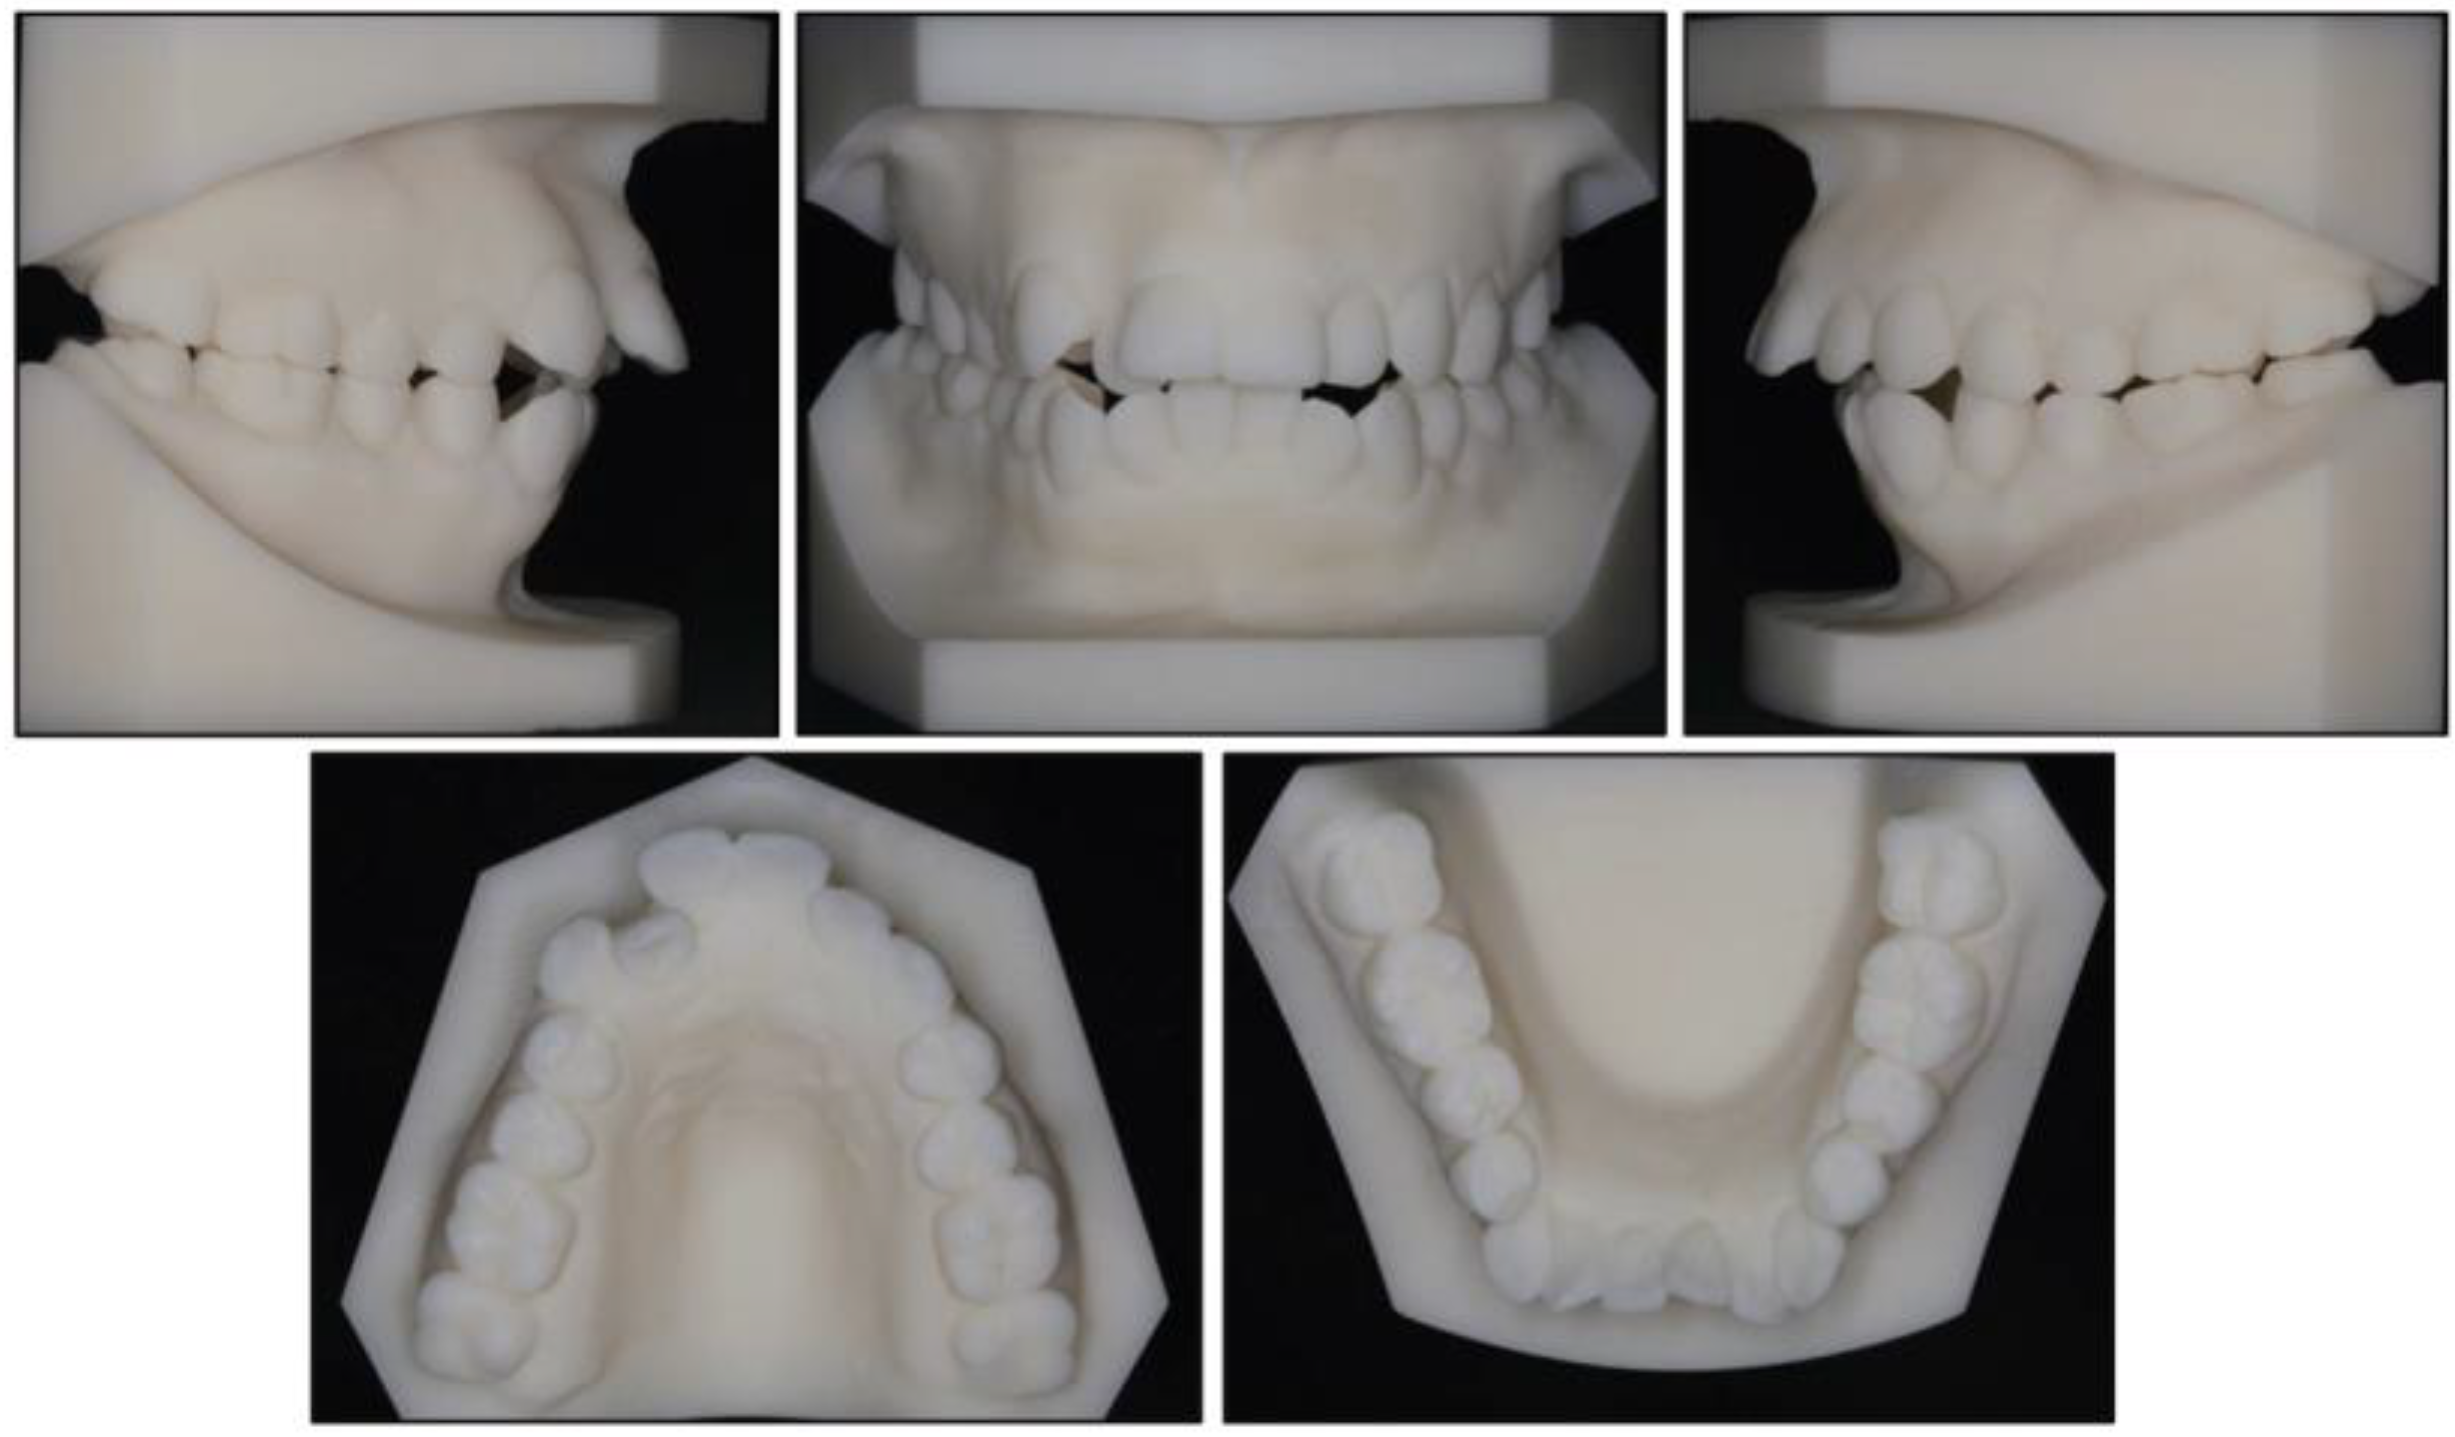

2.5. Treatment Results